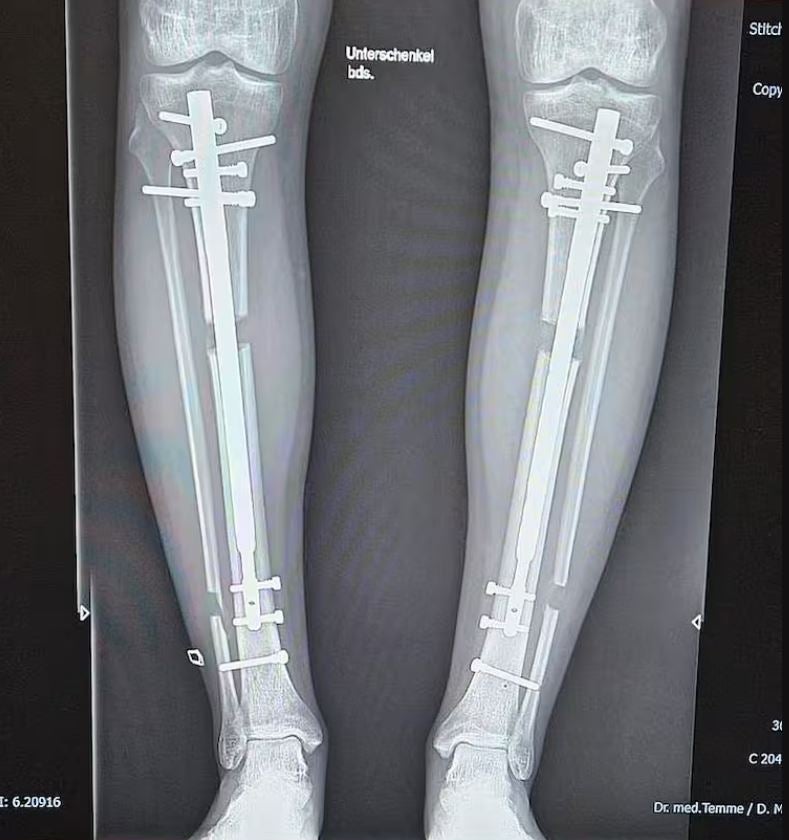

Influencer Leon Otremba (23) ließ sich in zwei aufwändigen Operationen die Beine um insgesamt 24 Zentimeter verlängern – von 171,5 auf aktuell 192 Zentimeter.

Grund dafür war seine tiefe Unzufriedenheit mit seiner Körpergröße, die ihn nach eigenen Aussagen in seinem Selbstbewusstsein stark einschränkte. Die erste OP fand 2023 in einer türkischen Klinik statt und kostete rund 35.000 Euro – die Hälfte zahlte sein Vater. Trotz monatelanger Schmerzen, Physiotherapie und Gehen auf Krücken unterzog sich Otremba Anfang 2025 einer zweiten Verlängerung.

Sein neues Ziel: 2,50 Meter Körpergröße – und damit der größte Mann der Welt zu werden.